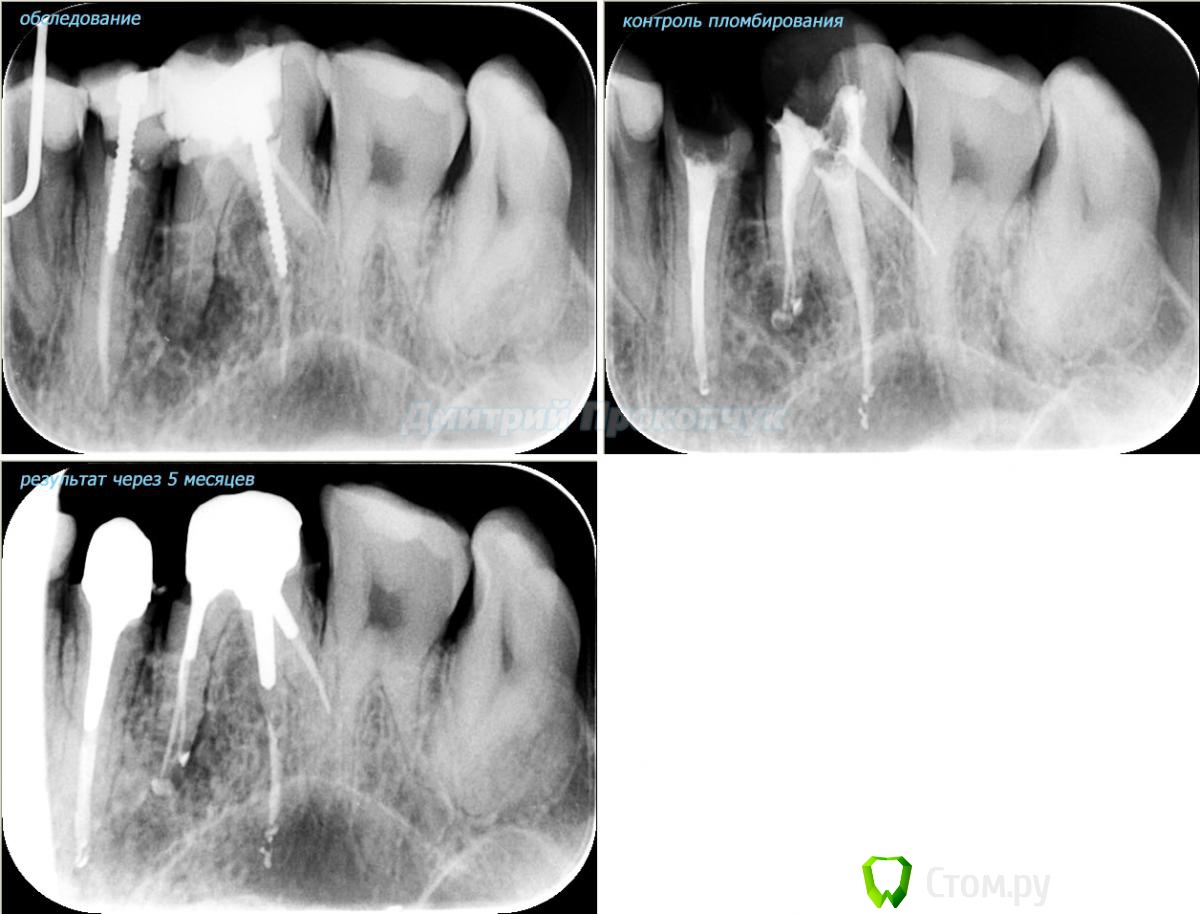

punkrat Опубликовано 16 сентября, 2014 Поделиться Опубликовано 16 сентября, 2014 Коллеги, тема , возможно, не имеет смысла просто приятная мне эндодонтия, сохранил с предыдущего места работы. Да, будь я проклят, я все знаю, НИГДЕ НЕТ КОФЕРА, на новом месте с этим норм. В общем если посчитаете, что я недостоин постить тут свои снимки, то так тому и быть, удалю тему.. 01. плановый ретрит 46ого и результат через 7 месяцев. Осложняющим моментом тут было то, что длина каналов была около 26 мм... 02. первичное эндо 34 (подготовка к ортопедии) + бонус - ретрит 35 03. ретрит 26 (подготовка к ортопедии) 04. ретрит 15, 16 (подготовка к ортопедии). основная сложность была в ретрите 15 - он был запломбирован термафилами, да еще снабжен свш... 05. ретрит 27 (подготовка к ортопедии). Ничего особенного, со временем посмотрим какова будет убыль этого совсем немаленького разрежения 06. ретрит 13. Разумеется пришлось выбивать вкладку, а потом еще попилить 3-4 миллиметра цемента, но, таки попилил куда нужно... 07. ретрит 17 (подготовка к ортопедии). В данном случае я, кажется, потратил больше времени на снятие литого моста, чем на лечение 17)) 08. ретрит 16 (подготовка к ортопедии). Снимка с инструментом нету, поскольку, визиограф сломался и его делал на пленку. 15 разумеется тоже перелечен... 09. плановый ретрит 16 10. первичное эндо 36, рядовой случай что дистальный щечный удалось найти не сразу, он был спрятан под нависающим дентиклем 11. ретрит 12, 11 (подготовка к ортопедии). Казалось бы, рядовой случай, если бы корневые каналы обоих зубов не были бы налухо забиты резорцин-формалиновой смесью... 12. ребенок 9ти лет, острый пульпит 46, попробовал оставить витальным. Пока полет нормальный, но даже если придется делать эндо в последствии, лучше когда оно будет сделано в более старшем возрасте... 13 Ссылка на комментарий

Dr.Sham Опубликовано 19 октября, 2014 Поделиться Опубликовано 19 октября, 2014 Коллеги, спасибо, я не ожидал, прям счастлив))) С нового места как подсоберу интересных работ некоторое количество, обязательно выложу. Еще есть несколько кейсов со старого места, такие уже скажем средней степени сложности, только надо будет в фотошопе оформить в единую пикчу. Про паффы все знаю, причина в термафиле + есть у меня бзик, что если аплок не пищит верхушку, считаю что не дошел, и пытаюсь додолбить и в связи с этим иногда апекс подразбиваю в итоге обработки.Алгоритм странный. Если апекс не пищит - додолбить. А чем? и где гарантия, что это верхушка, а не перфа в апикальной части? мы же знаем, что рентгенологическая верхушка лишь в небольшом % случаев совпадает с физиологической. На большинстве снимков очаг вроде уменьшился - субъективно, но не исчез. 7 месяцев - это срок. Ссылка на комментарий

SSTi Опубликовано 19 октября, 2014 Поделиться Опубликовано 19 октября, 2014 На большинстве снимков очаг вроде уменьшился - субъективно, но не исчез. 7 месяцев - это срок. Часто вы видите полное восстановление через 7 месяцев??? Это не срок. 1 Ссылка на комментарий